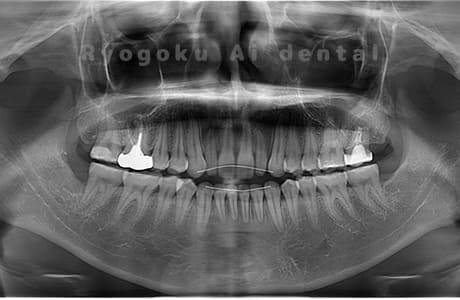

Case02

- 原因

- 下顎の水平埋伏智歯

- 治療内容

- 下顎の水平埋伏智歯を抜歯

<リスク・副作用>

手術後は痛み、腫れ、痺れなどの副作用が生じる場合があります。